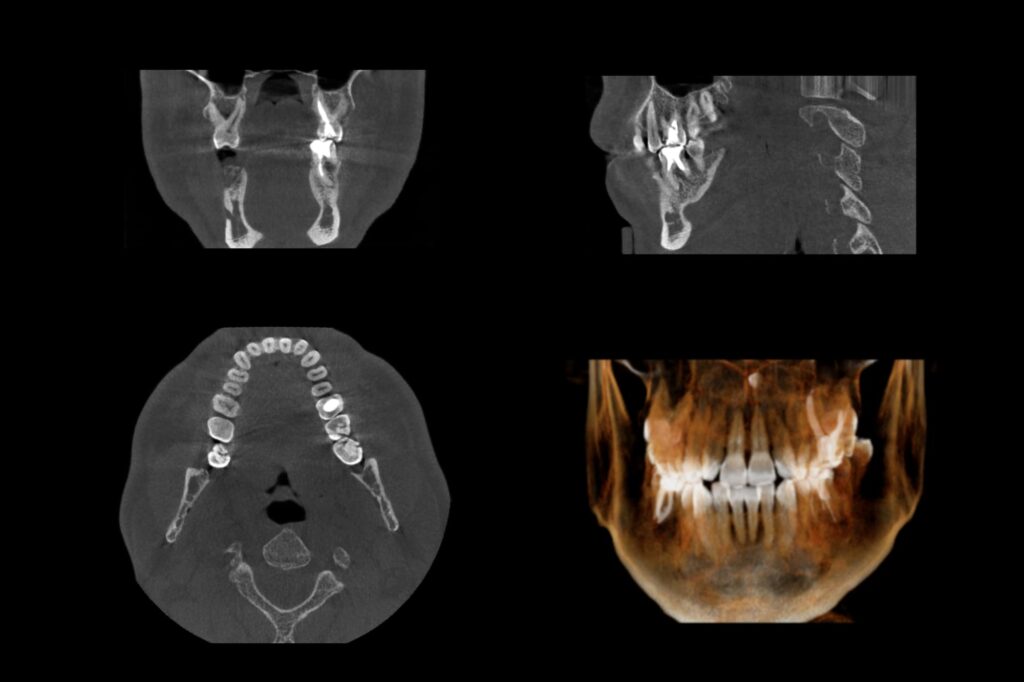

CTによる三次元的な診断

二次元レントゲンでは確認できない小さな病変も、CTを用いることで三次元的に把握できます。問題部位の見落としを防ぐことで、より確実な診断と治療計画の立案につながります。

CT画像

レントゲン画像